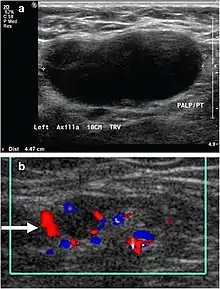

- Absence of the fatty hilum

- Increased focal cortical thickness greater than 3 cm

- Doppler ultrasonography that shows hyperaemic blood flow in the hilum and central cortex and/or abnormal (non-hilar cortical) blood flow.[24]

On ultrasound, B-mode imaging depicts lymph node morphology, whilst power Doppler can assess the vascular pattern.[26] B-mode imaging features that can distinguish metastasis and lymphoma include size, shape, calcification, loss of hilar architecture, as well as intranodal necrosis.[26] Soft tissue edema and nodal matting on B-mode imaging suggests tuberculous cervical lymphadenitis or previous radiation therapy.[26] Serial monitoring of nodal size and vascularity are useful in assessing treatment response.[26]

Lymphadenopathy of the axillary lymph nodes can be defined as solid nodes measuring more than 15 mm without fatty hilum.[34] Axillary lymph nodes may be normal up to 30 mm if consisting largely of fat.[34]

Lymphadenopathy of more than 1.5–2 cm increases the risk of cancer or granulomatous disease as the cause rather than only inflammation or infection. Still, an increasing size and persistence over time are more indicative of cancer.[37]